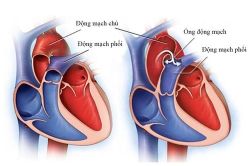

Teo van động mạch phổi là một dạng dị tật bẩm sinh, trong đó van động mạch phổi (van tim nằm giữa tâm thất phải và động mạch phổi) không hình thành mà thay vào đó tim được ngăn cách với động mạch phổi bởi một lớp mô rắn. Teo van động mạch phổi thường được phát hiện ngay sau khi sinh.